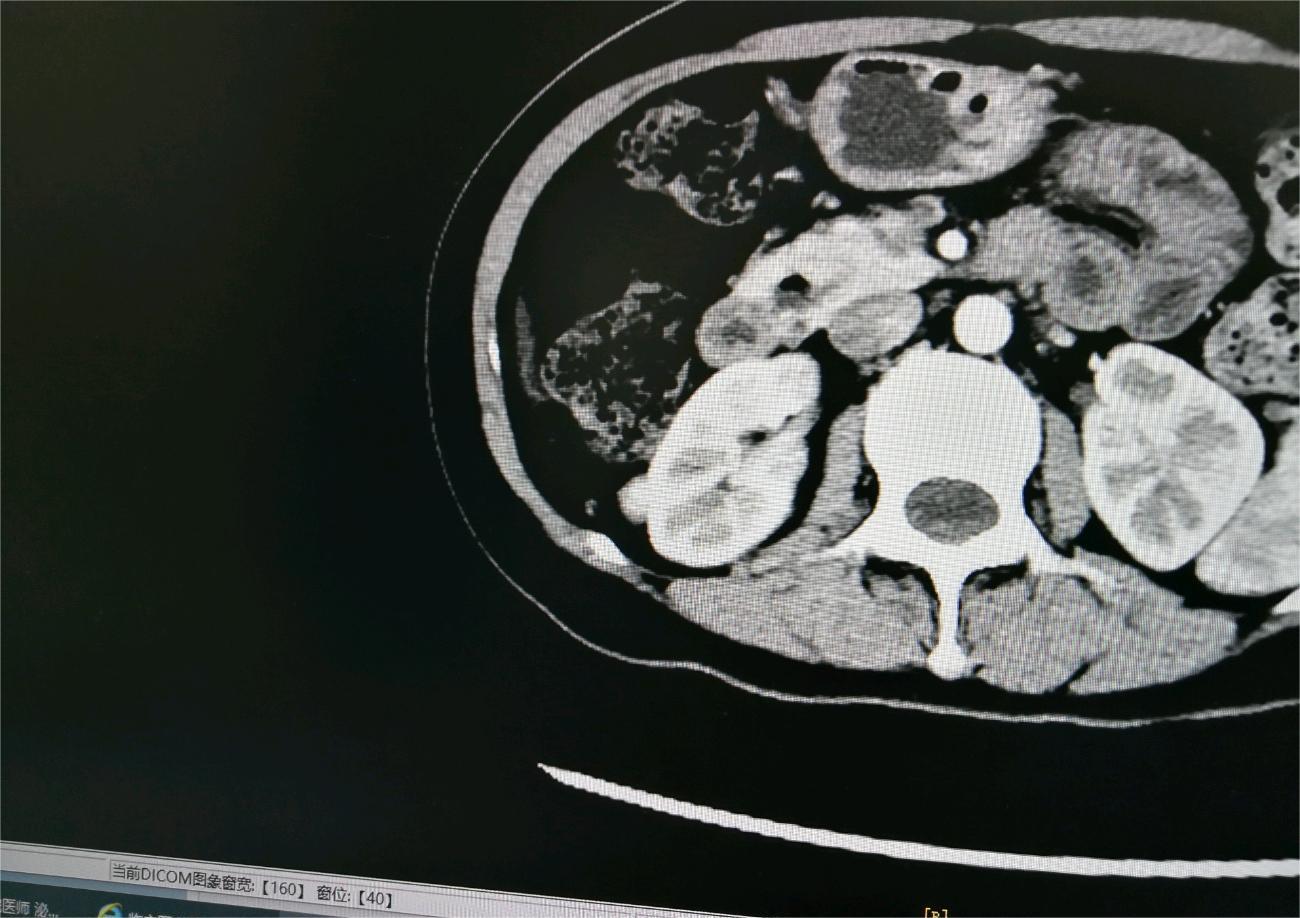

Here 02024-12-05 患者33岁,刚查出怀疑肾癌,麻烦有懂行的大神给分析一下,我是属于早期的吗?肾癌存活率是多少?有一个孩子,刚刚10个月。